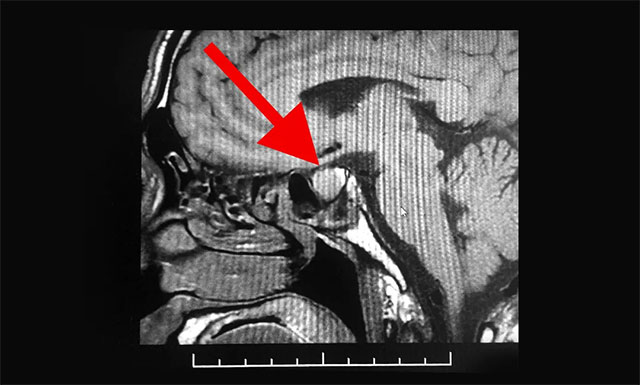

管先生因为咳嗽严重,于3月20日就诊于浙江省某医院,当时挂的是呼吸科,经过检查,医生说有些炎症,吃些咳嗽药就可以了。但与此同时,医生却发现管先生的鼻子、手部和指关节都要比常人大很多,遂建议他去脑外科检查,随后他在该医院又进行了头部MRI检查,根据影像检查结果,并结合其临床症状,患者最终被确诊为垂体瘤。

潘仁龙主任表示,患者容貌及四肢已发生很大改变,其四肢指关节粗大,声音嘶哑,结合其影像检查结果,手术指征明显,应尽早诊疗。

管先生这次手术是由经验丰富的李士其教授主刀,李教授擅长神经外科常见疾病-垂体腺瘤的显微外科治疗,尤其是经蝶窦手术入路的垂体腺瘤微创手术。随后,在征得家属同意,手术准备就绪后,于4月3日,李士其教授、潘仁龙主任及吴治群博士组成的专家团队,顺利为患者实施了手术。术中,见淡黄色肿物,质软,与周围垂体边界较清楚,在蔡司显微镜(双荧光)下将鞍内肿物切除,其肿瘤大小约为1.5厘米×1.5厘米×1.5厘米,部分呈囊性,留取肿物送检病理。